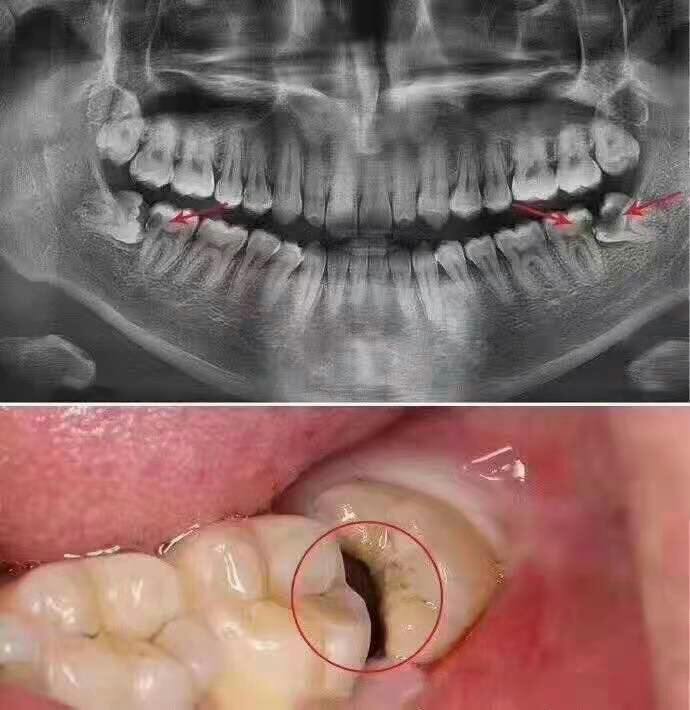

2、不易清洁的智齿

不易清洁的智齿,食物残渣长期滞留在口内,造成细菌滋生,不仅容易出现口臭,还会导致牙齿龋坏。

3、横向阻生的智齿

横向阻生的智齿容易将邻牙挤压后,造成邻牙受损,甚至还易导致牙齿变得拥挤不齐,清洁难度加大,提高齿病的发生几率。